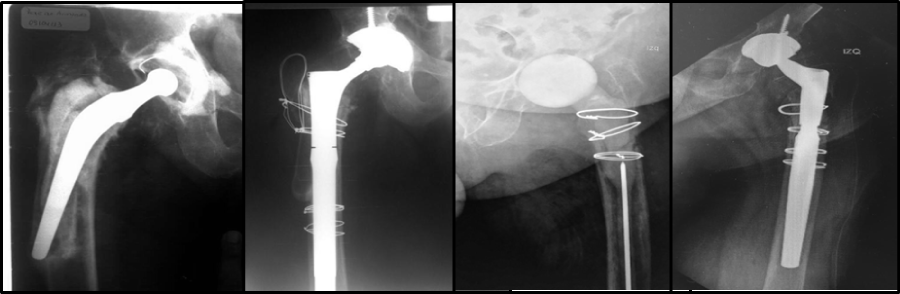

Radiographic control at 6 years postoperative showed no subsidence of the implant and adequate integration.

Case 2

A 4-year postoperative follow-up of the conversion revealed implant integration without radiographic subsidence. In both cases presented, a reduction in the diameter of the femoral isthmus was achieved, allowing good axial and rotational stability of the uncemented modular stem, with the respective follow-up of 6 and 4 years showing complete osseo integration without evidence of sinking radio graphically (Figure 3).